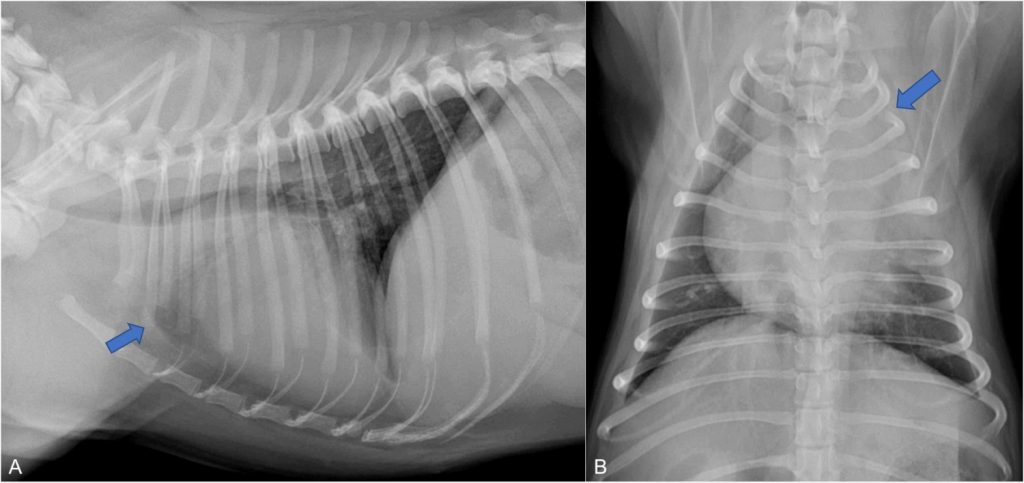

La consolidación pulmonar (fechas) es un signo que aparece en estos casos, pero también en casos de neumonía grave, neoplasia infiltrativa, hemorragia o tromboembolismo pulmonar.

En un estadio temprano el lóbulo afectado tiene mayor tamaño y con márgenes redondeados por la congestión pasiva que sufre al colapsarse inicialmente la vena pulmonar. En una fase más avanzada el volumen del lóbulo pulmonar disminuye por la necrosis del lóbulo afectado.